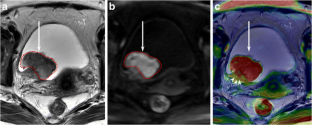

Fig. 2